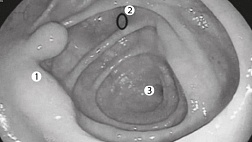

Вы выполняете, приближенное к реальности, обследование бронхиального дерева в HDTV качестве бронхоскопом BF-H190.

Реализована функция внутрипросветной эндонавигации по бронхиальному дереву!

Вы сможете последовательно начиная от карины, используя тачскрин, выбирать направление и изучать\вспоминать анатомию бронхиального дерев

Комментарии диктора статичных изображений и переходные видео применены для максимального облегчения пространственной ориентации и подробного объяснения о ангуляции и движении бронхоскопа во время исследования.ВИДЕО работы приложения можно посмотреть на сайте разработчика:

Anatomy training tool

Описание

You are welcome to experience a bronchoscopic examination, almost as if it were done in a real clinical setting. Starting at the main carina, this app enables you to steer a HDTV bronchoscope through the bronchial tree step-by-step, from one carina to the next. Audio commentated still images and transitional videos are displayed facilitating spatial orientation and providing detailed explanation about the angulation and movement of the bronchoscope. Highly experienced medical experts have been involved in the development of this training app; however, please keep the following aspects in mind: